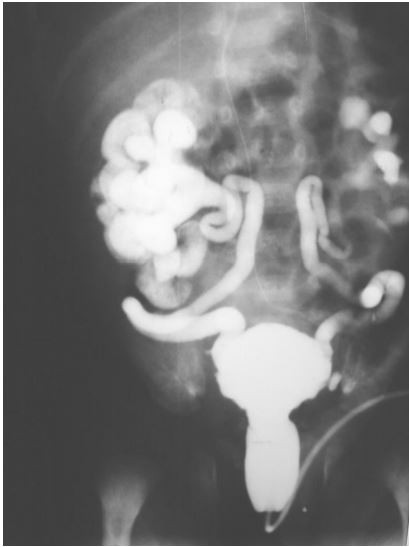

Lactente masculino apresenta infecção urinária de repetição e sepse. Tem diagnóstico pré-natal de hidronefrose bilateral. Realizou este exame radiológico contrastado.

Pode-se afirmar que: